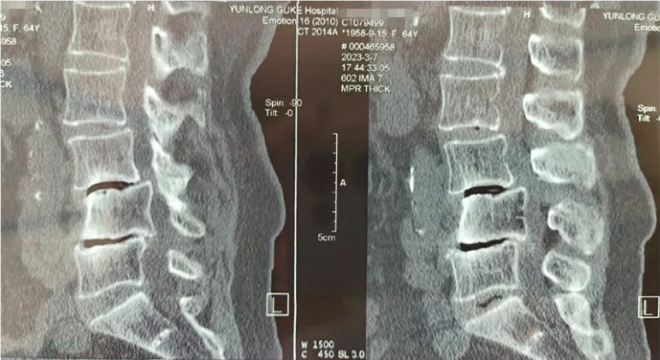

患者术前影像资料

通过影像学资料结合查体,王某诊断为"腰椎滑脱 腰椎管狭窄"。影像资料提示,王某腰L4椎体滑脱,腰L4-L5间隙变窄,椎间盘突出,椎管狭窄,神经根受压。